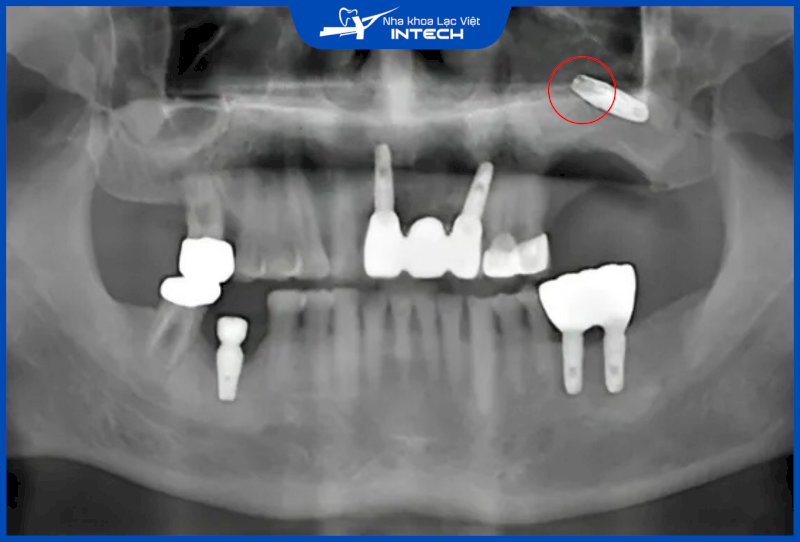

Thông thường, cô chú/anh chị cần nâng xoang khi chiều cao phần xương hàm còn lại quá thấp (dưới 8mm), do mất răng lâu ngày gây tiêu xương và xoang hàm bị sa xuống. Trong trường hợp này, nếu không nâng xoang mà đặt trụ Implant, trụ có thể không đủ độ vững chắc hoặc thậm chí xuyên vào xoang gây ra các biến chứng nguy hiểm.

Khi cắm Implant hàm trên, nếu bác sĩ xác định sai độ sâu thì có thể cắm Implant âm phạm xoang hàm, gây nên nhiều biến chứng nguy hiểm